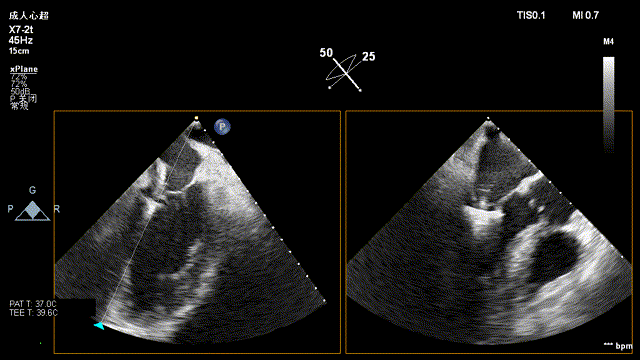

全超声引导下TEER

导丝进行房间隔穿刺:

CDS放置在二尖瓣处:

打开夹子,调整弹道垂直于二尖瓣瓣环:

将MitraClip推进至左心室,捕获瓣叶:

捕捉瓣叶后,经超声心动图确认瓣叶夹持牢固,释放瓣膜夹: